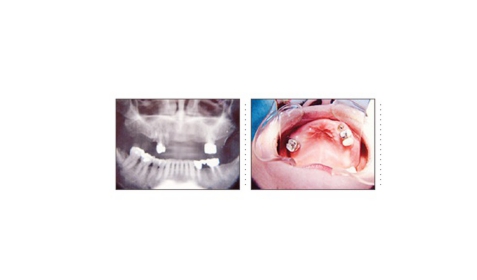

最近はインターネットの情報から来院される方が増えています。インプラント治療に関する知識も豊富で日本中の主だったインプラント歯科医院のホームページをチェックしている方もおります。この方もホームページをご覧になり来院されました。ご自分と同じような症例があり、しかも手術が短時間で痛みが無いのが選択理由だったようです。顎骨の質・量ともに十分でインプラント埋入は簡単です。CT撮影後、インプラント埋入シュミレーションソフトを使用すれば埋入はそれ程難しくはありません。ただ上顎の骨吸収がかなりあり歯の配列がとても難しいケースでした。

症例7

69才 女性

上顎骨がかなり減っていて、骨質・骨量共にインプラント治療には難しいケースです。

CT撮影後、埋入シュミレーションソフトで十分に検討します。このようなケースを成功させるには、患者さんの理解と協力が必要です。 下顎前歯が前突している為、抜髄しポーセレン冠で内側に配列。上顎前歯部・小臼歯部付近は骨幅が狭く、苦肉の策としてミニインプラントを使用。インプラントアバットメントの平行性、前歯の配列を考えると一般的には床を付けたインプラント義歯となります。装着感、審美性を考慮してブリッジにこだわりました。